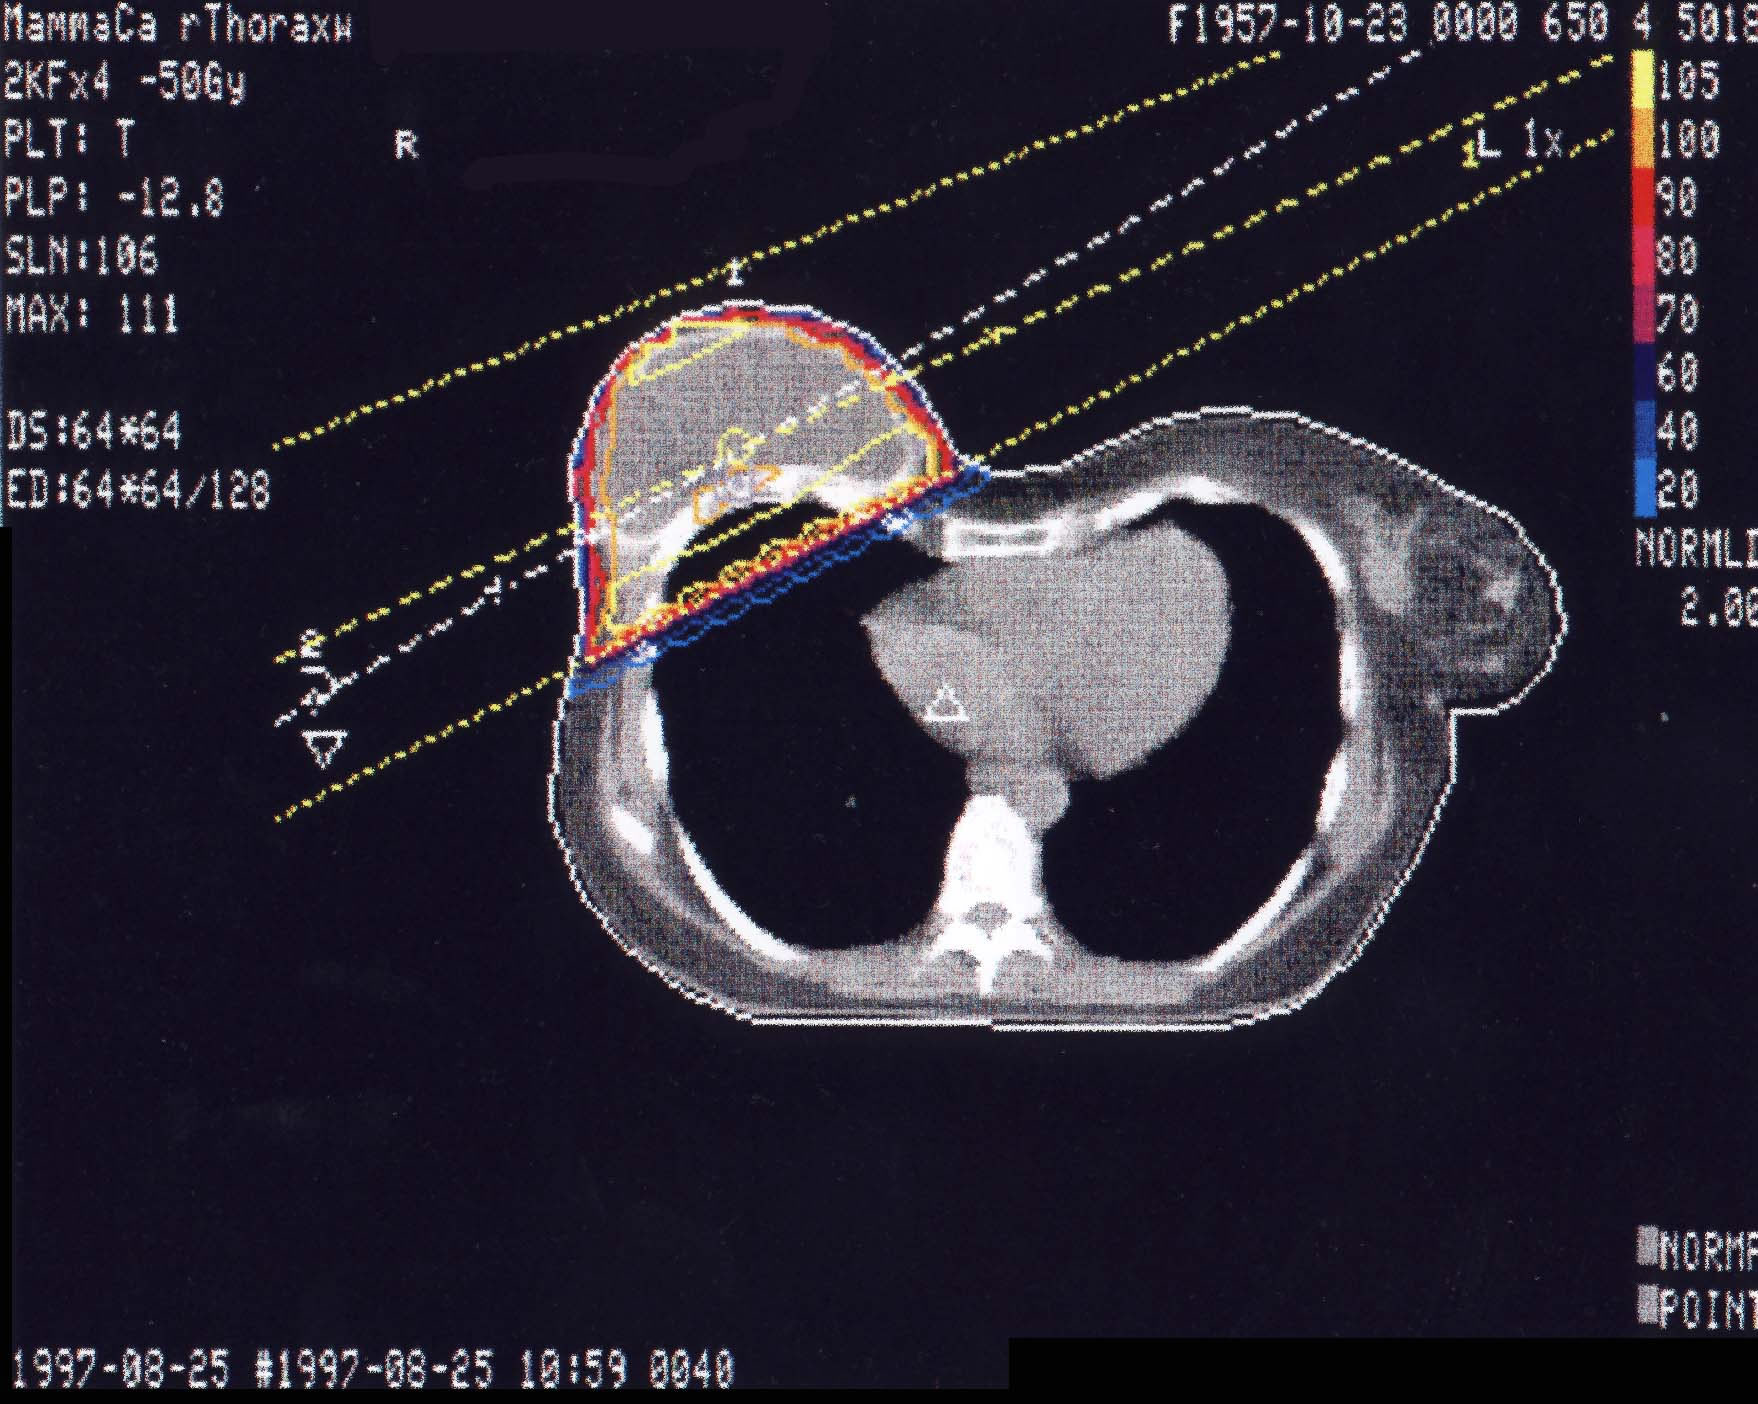

Mammakarzinom: Bestrahlungsplan

Bestrahlungspläne